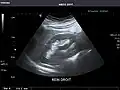

Renal ultrasonography

Ultrasonography of the kidneys is essential in the diagnosis and management of kidney-related diseases. The kidneys are easily examined, and most pathological changes in the kidneys are distinguishable with ultrasound.[7]

Kidneys: Right and left kidneys measure 11.5 cm and 12 cm in length respectively. No hydronephrosis. Small left lower pole kidney cyst.

Left kidney -